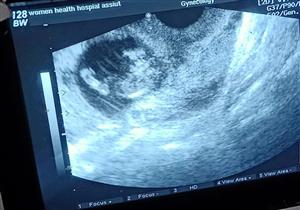

حمل خارج الرحم